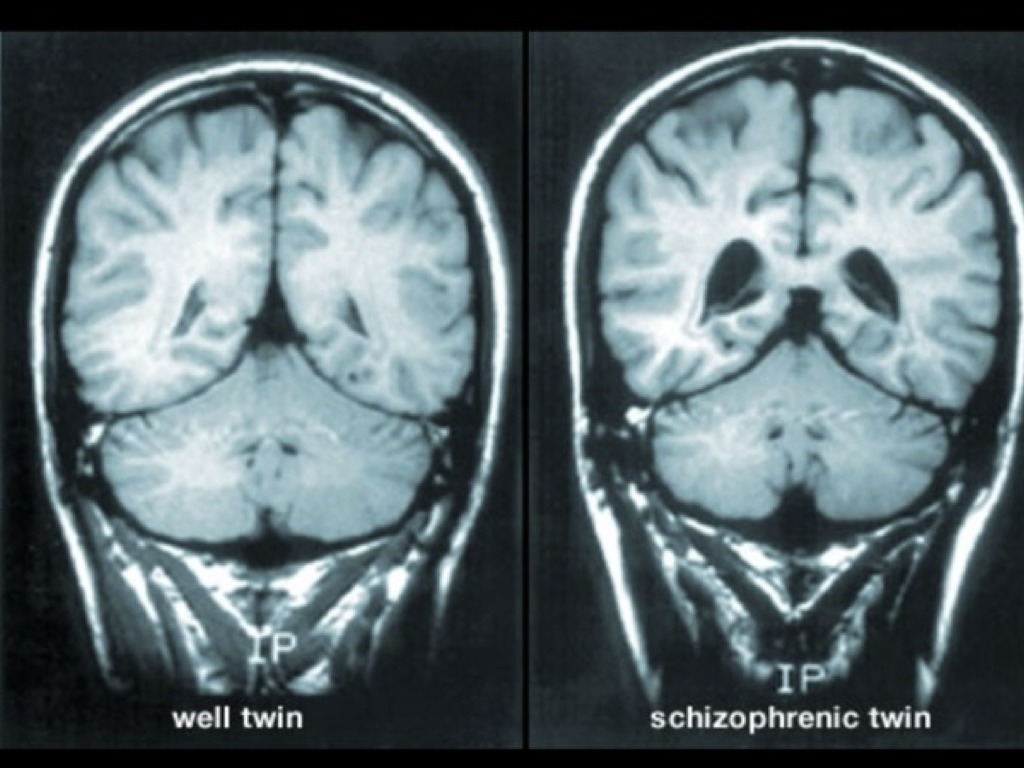

BRAIN ABNORMALITIES

50% CHANCE OF SUFFERING IF THEIR IDENTICAL TWIN HAS THE DISEASE